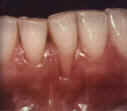

- Recession of the gums - Movement of gums away from the tooth due to periodontal disease will expose the root surface.

- Gum disease - Inflamed and sore gum tissue may also cause sensitivity due to the loss of supporting ligaments which exposes root surface.